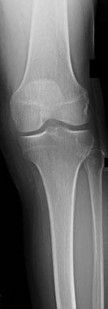

Question 18

A 60-year-old male presents with isolated medial compartment knee osteoarthritis and is being evaluated for a unicompartmental knee arthroplasty (UKA). According to classical indications (Kozinn and Scott), which of the following is considered an absolute contraindication to a fixed-bearing UKA?

Explanation

Classical criteria for unicompartmental knee arthroplasty (UKA) include an intact anterior cruciate ligament (ACL). ACL deficiency leads to altered knee kinematics, specifically paradoxical anterior translation of the tibia during flexion, which results in accelerated posterior polyethylene wear and early failure of a fixed-bearing UKA. While some modern surgeons perform UKA in ACL-deficient knees using mobile-bearing designs or concurrent ACL reconstruction, an absent ACL remains a classic board-tested contraindication for standard UKA.